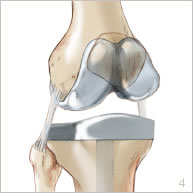

La prothèse comporte trois parties : la partie fémorale, la partie tibiale et la partie rotulienne (figures 4 et 6). Elle est implantée de manière à assurer une stabilité parfaite du genou et une mobilité la plus complète possible. Son bon positionnement peut être contrôlé par l’assistance informatique.